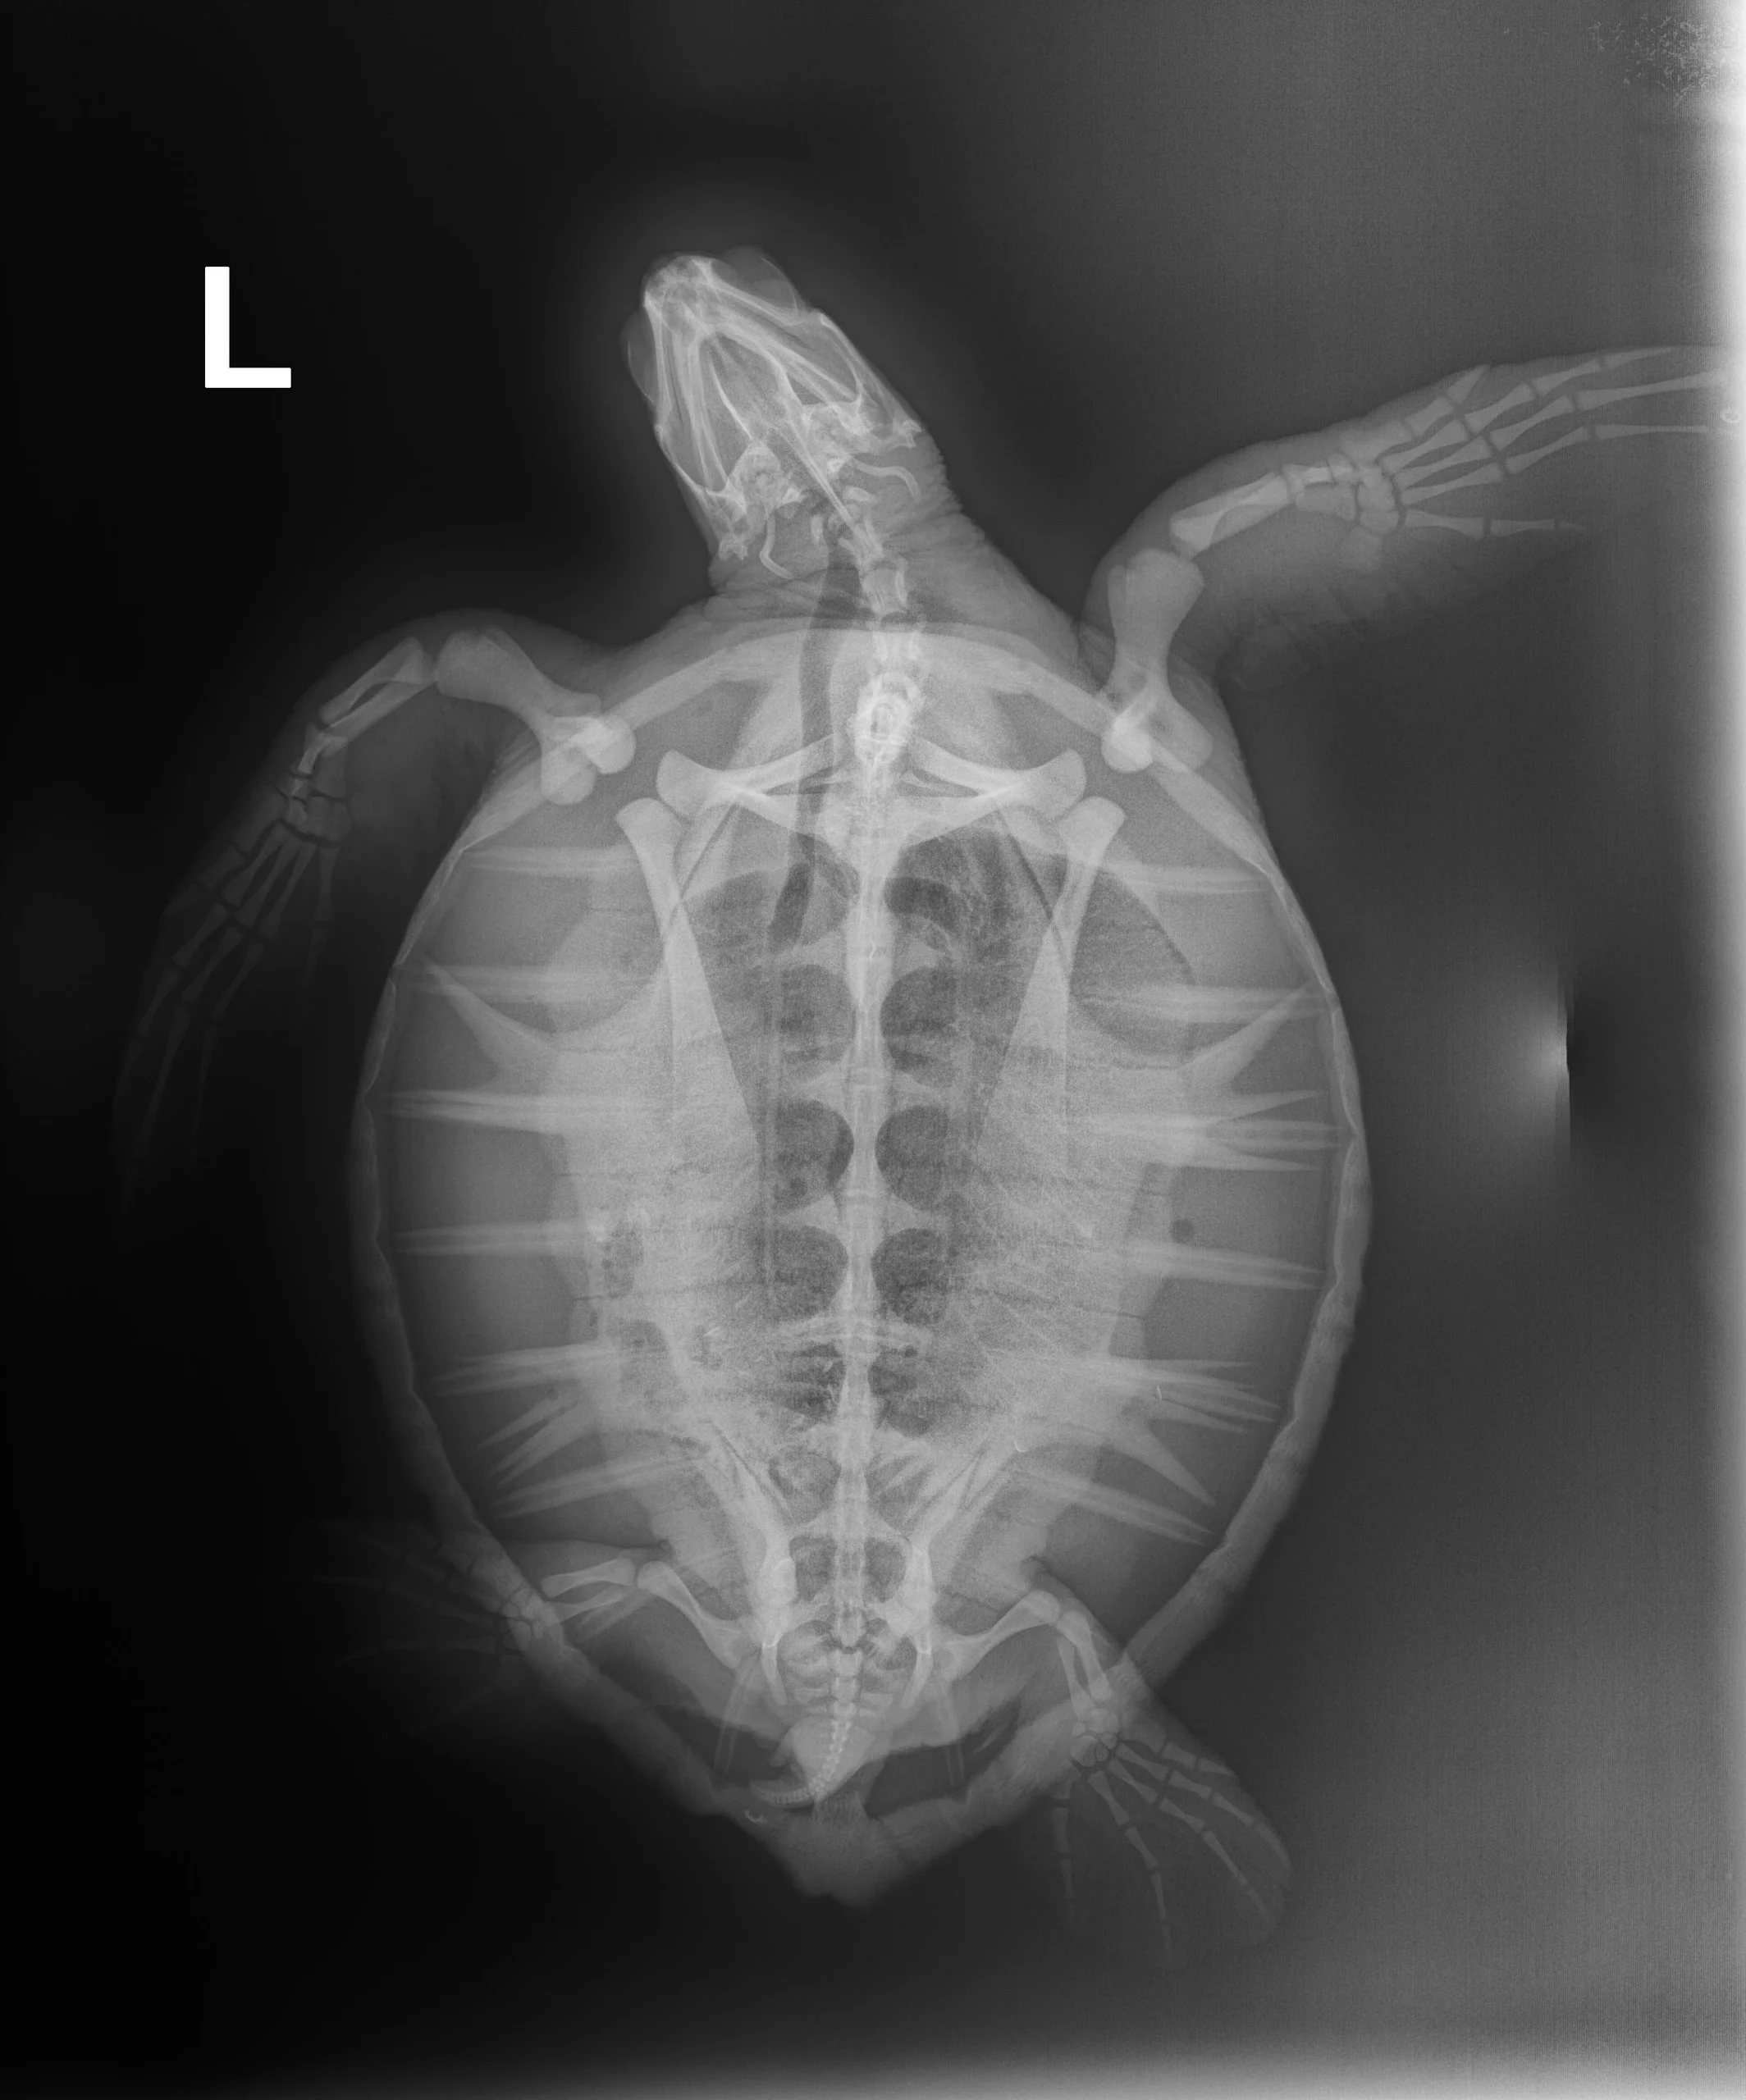

2.05 kg juvenile Atlantic Green sea turtle

Patient Injuries

External Carapace Notes: Notch on left marginal neat tip

Plastron: Minor abrasions

External Wounds: Small wound on right front flipper Lightly bleeding